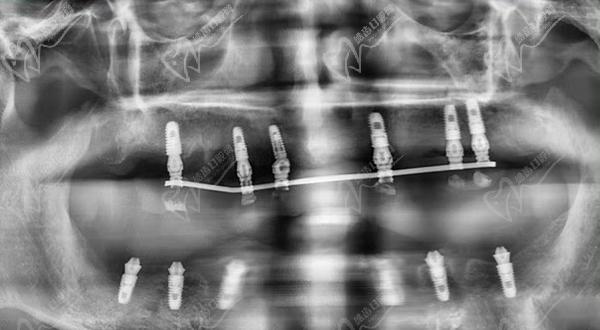

1、術(shù)前檢查和評估:進(jìn)行X光片、CT等影像學(xué)檢查,以確定患者的牙槽骨質(zhì)量和數(shù)量,為手術(shù)方案的指定提供數(shù)據(jù)支持。一般家里的老人患有基礎(chǔ)疾病的只要身體健康、口腔條件達(dá)標(biāo)都可以做,對全口牙齒重度松動的中青年患者亟需修復(fù)的可以做。

重度牙周炎會導(dǎo)致牙齒松動、脫落和牙槽骨的破壞。全口即拔即種種植牙適用于牙周炎患者,可以在一次手術(shù)中同時(shí)拔除松動的牙齒并植入種植體。在手術(shù)前,需要進(jìn)行詳細(xì)的口腔檢查和評估,包括X光片、CT等影像學(xué)檢查,以確定患者的牙槽骨質(zhì)量和數(shù)量。在手術(shù)中,局部麻醉后拔除松動的牙齒,然后在拔牙后的創(chuàng)口內(nèi)植入種植體,并進(jìn)行縫合。術(shù)后需要指導(dǎo)患者進(jìn)行日常護(hù)理和藥物治療,確保創(chuàng)口愈合良好。